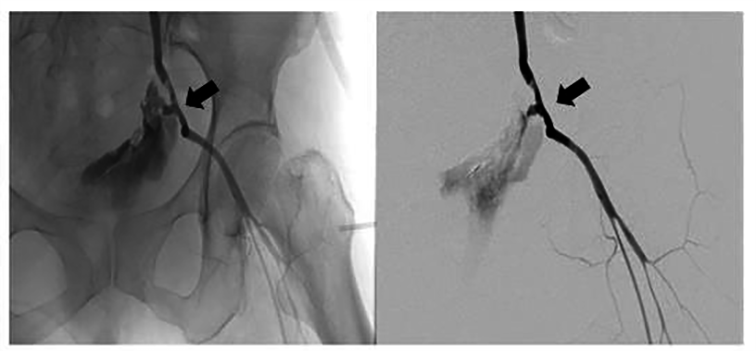

Internal jugular central venous catheterization, massive blood transfusion and

drugs administration were done as an emergency exploratory interventional

surgical was performed simultaneously. Bilateral renal artery angiography showed

no vascular anomalies and contrast spillover. However, there was obvious contrast

agent spillover on the left external iliac artery (Fig. 2). The patient was

diagnosed with a ruptured left external iliac artery pseudoaneurysm. A covered

stent, measuring 8 mm

Fig. 2.Angiography showed obvious contrast agent overflow from ruptured pseudoaneurysm on the left external iliac artery (arrow).